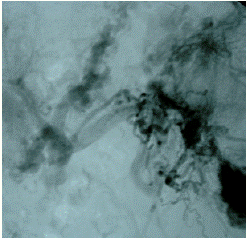

Портография через внутреннюю яремную вену – инвазивный, но очень точный метод диагностики. Он позволяет оценить протяженность тромбоза, его точную локализацию и выраженность тромботического стеноза воротной вены [5, 9, 10]. (см. Рисунок 3).

Рисунок 3. Спленопортография показывает каверноматозную трансформацию с извитыми порто-системными коллатералями и выраженные варикозно расширенные вены пищевода и желудка.